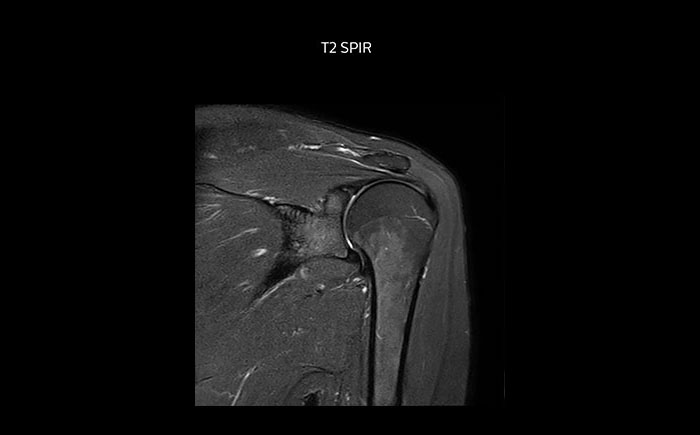

The Prodiva shoulder coil is very flexible and has large coverage, which makes good positioning easier, and that contributes to the superb image quality and high SNR that we get in our shoulder exams.

Scan time 2:55 min, FOV 160 mm, acq voxels 0.55 x 0.83 x 3.0 mm.